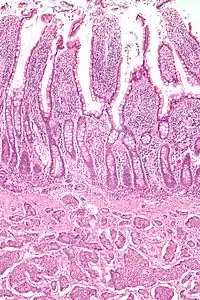

| Micrograph of a neuroendocrine tumor. H&E stain | |

NETs are often small, yellow or tan masses, often located in the submucosa or more deeply intramurally, and they can be very firm due to an accompanying intense desmoplastic reaction. The overlying mucosa may be either intact or ulcerated. Some GEP-NETs invade deeply to involve the mesentery.[72] Histologically, NETs are an example of "small blue cell tumors," showing uniform cells which have a round to oval stippled nucleus and scant, pink granular cytoplasm. The cells may align variously in islands, glands or sheets. High power examination shows bland cytopathology. Electron microscopy can identify secretory granules. There is usually minimal pleomorphism but less commonly there can be anaplasia, mitotic activity, and necrosis.